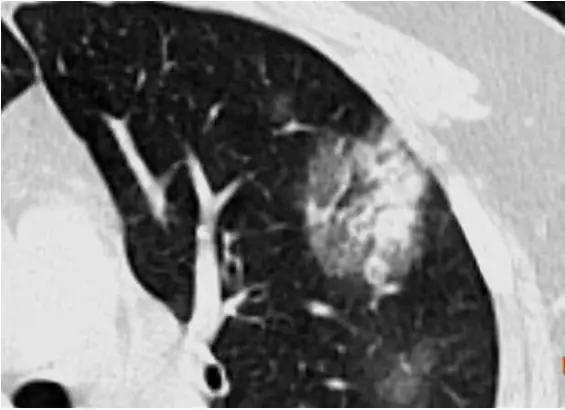

病例 5 女性,35 岁,发热待查

左肺上叶斑片状渗出、部分实变,内见支气管充气征